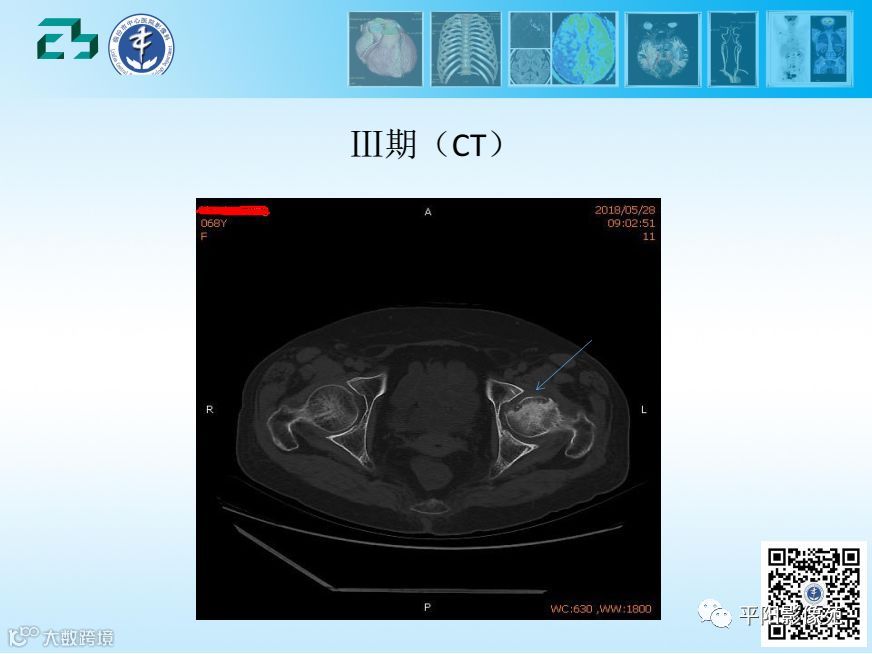

【影像基础】股骨头缺血坏死分期